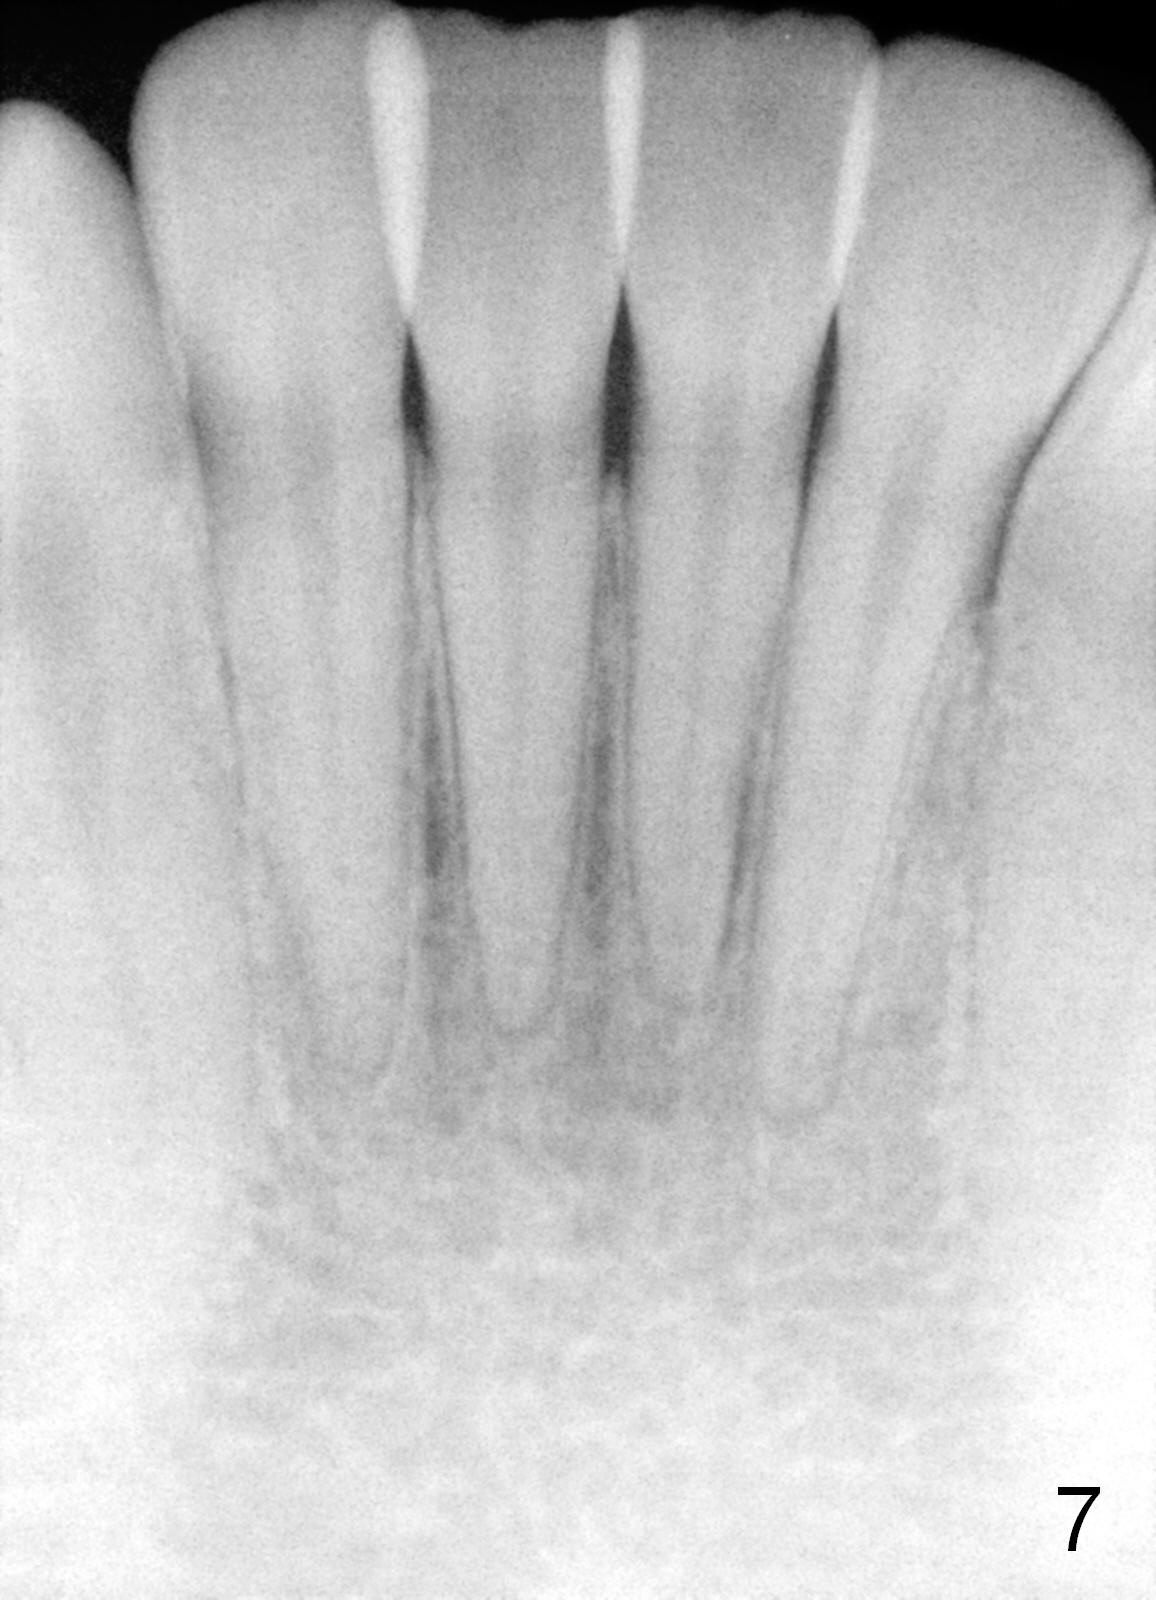

The panoramic X-ray (Fig.1) was taken on 12/12/2011 when the teeth #15 and 16 were extracted. The teeth #1 and 2 were removed half a year later. Bitewings (Fig.2-5), PAs (Fig.6,7) and upper occlusal mirror photo were taken on 02/11/2015. Pay attention to Fig.2.